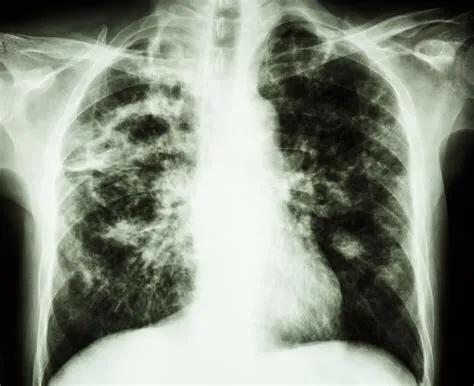

肺结核的胸部X线表现

结核病

在有些疾病中,盗汗是唯一的首发症状,比如前面说到的肺结核。

结核病,是在医学领域中与盗汗相关性最大的疾病。

针对确诊结核病的成人患者的调查研究发现,约46%~62%的患者有盗汗的症状,其中29%的患者盗汗持续两周。

肺以外脏器的结核,比肺结核患者更经常出现盗汗,发生率超过50%。

结核病的其他表现有咳嗽、疲劳、发热、体重减轻、食欲减退、胸痛、腹泻、咳血等等。

年轻的患者比年老的患者更容易出现盗汗。

艾滋病患者同时合并肺结核时,盗汗往往更加明显。

肺结核